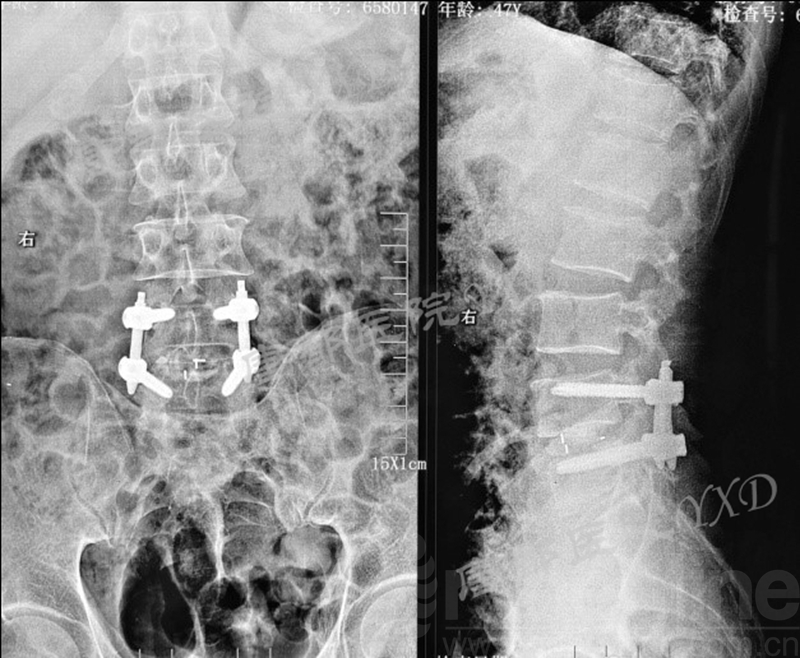

患者47岁,男性。

主诉:腰椎术后左下肢疼痛2月。

专科情况:跛行入病房;左侧直腿抬高试验阳性(60°)、加强试验阳性;左侧足背伸肌力、踇趾背伸肌力3级;左小腿外侧及足背皮肤感觉明显减退;余未见明显异常。VAS评分:左下肢7~8。

既往于半年前因“腰椎间盘突出症(L4-5)”于外院行腰椎侧路脊柱内镜下髓核摘除术(L4-5)。后因症状复发,分别在2周前、10天前于外院行两次腰椎后路脊柱内镜下髓核摘除术(L4-5)。

影像学检查:

诊断:腰椎间盘突出症术后复发

手术方案:显微镜辅助MI-TLIF腰椎翻修术

术中视频:http://api.orthonline.com.cn/attach/Case2.mp4(术中发现因前三次侧路及后路内镜手术的操作,术区大量瘢痕组织增生、与神经粘连严重;此外,摘除头侧游离髓核时连接有软骨终板脱落;在显微镜操作下,安全地将神经进行充分松解,压迫神经的游离髓核及软骨终板彻底清除。无手术并发症)

术后疗效:VAS评分左下肢1;左侧足背伸肌力、踇趾背伸肌力4级;左侧直腿抬高试验、加强试验阴性;行走自如、步态正常。